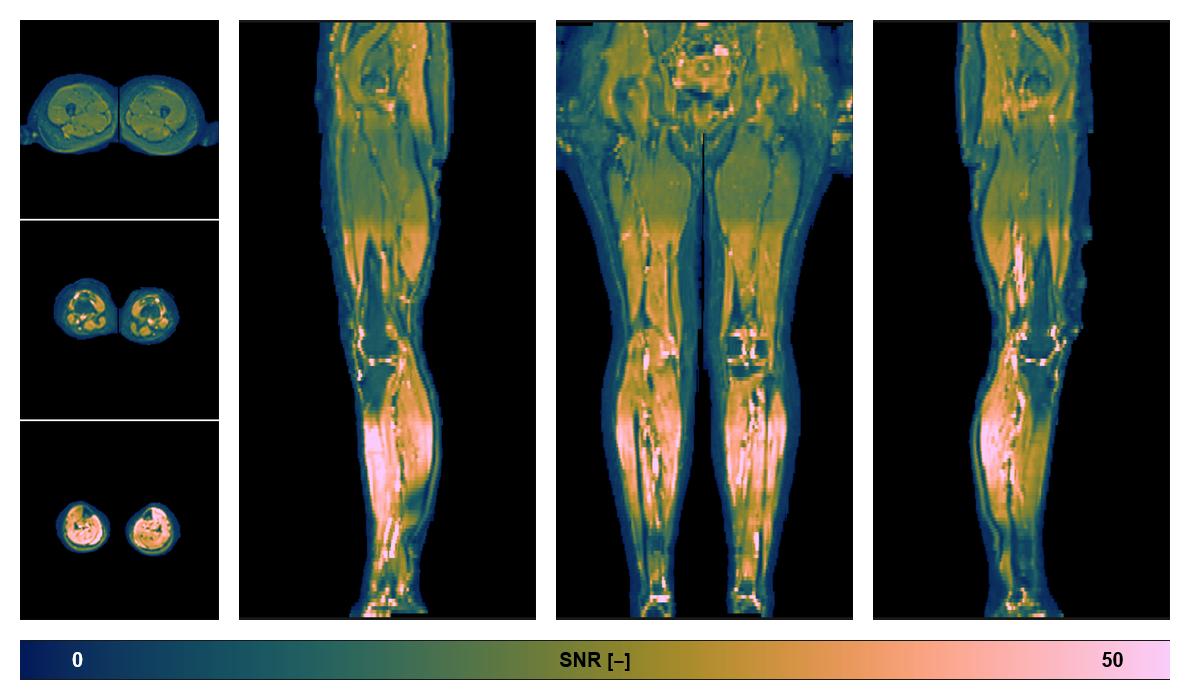

• SNR of the unweighted image

SNR distribution of the unweighted diffusion data.